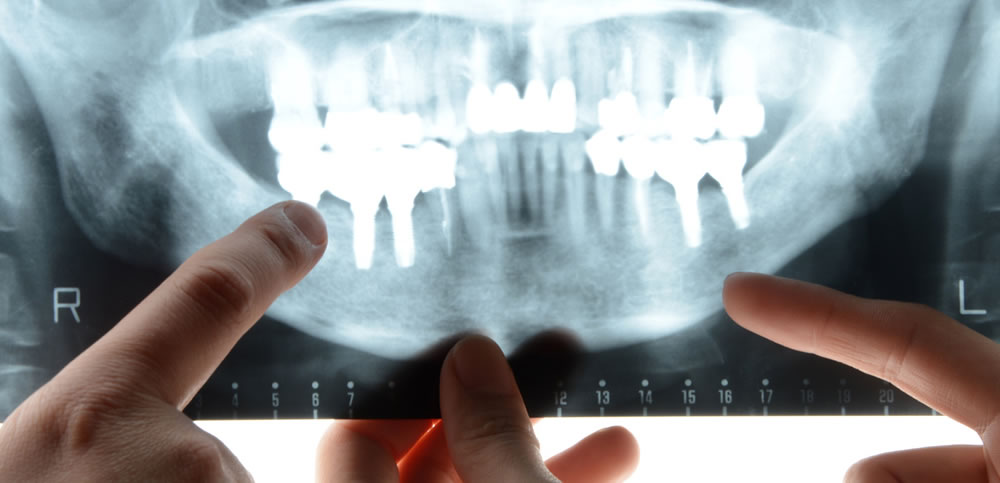

CTを駆使した精密検査

インプラント手術の際は、歯科用CTによる精密検査を実施いたします。

インプラント手術の際は、歯科用CTによる精密検査を実施いたします。

インプラントを埋入する部分の顎骨の状態や周辺の神経・血管の位置を把握し、適切な治療計画を立案します。

ガイドによる人為的ミスの防止

CT画像と専用のソフトによるシミュレーションを行い、そのデータを基に埋入位置や埋入角度など反映させたマウスピース型のガイドを製作します。

CT画像と専用のソフトによるシミュレーションを行い、そのデータを基に埋入位置や埋入角度など反映させたマウスピース型のガイドを製作します。

オペの際にガイドを用いることで、人為的ミスを防止し、シミュレーション通りの位置へインプラントを埋入することができます。